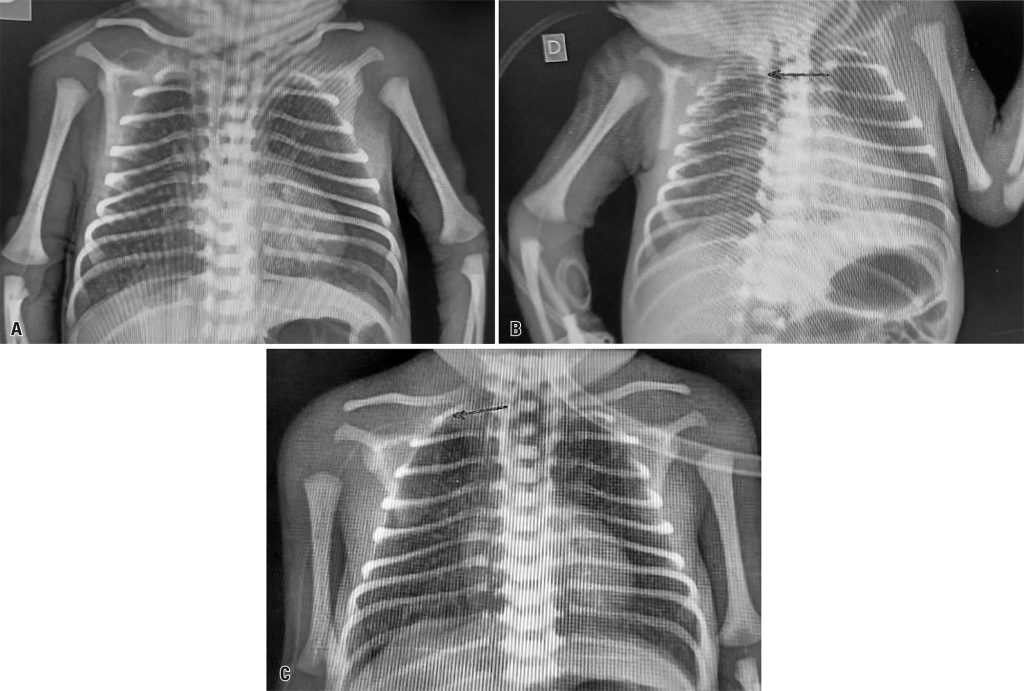

This article describes the occurrence of cardiac tamponade in a premature newborn after the use of a peripherally inserted central catheter at a university hospital in Brazil. Pericardiocentesis was performed, the catheter was repositioned using radiography, and minimal residual pericardial effusion was confirmed using echocardiography. The patient showed good progress and was discharged from the hospital on day 47 of life without any complications related to the event. Therefore, although adverse events may occur following the insertion of peripherally inserted central catheters, imaging examinations and exclusion diagnoses have a positive impact on clinical outcomes. This study emphasizes the importance of a multidisciplinary team for monitoring and managing adverse events and optimizing the care of critically ill newborns.